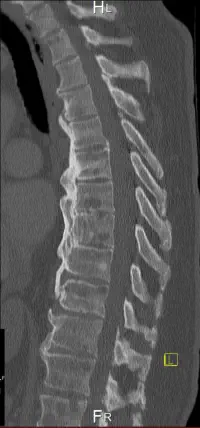

MRT und CT - Bilder - Auswahl

Osteoplastische Knochenmetastasen zeichnen sich dadurch aus, dass Krebszellen den Knochen angreifen und eine übermäßige Bildung von neuem Knochengewebe anregen, was zu einer Verdichtung und Sklerosierung des Knochens führt. Die jedoch die Knochenstabilität nicht verbessert. Die im Gegensatz zu Osteolytische Metastasen bei denen Knochen abgebaut wird. (Zum Beispiel Löcher, dünne Knochen und dünne Knochenränder)